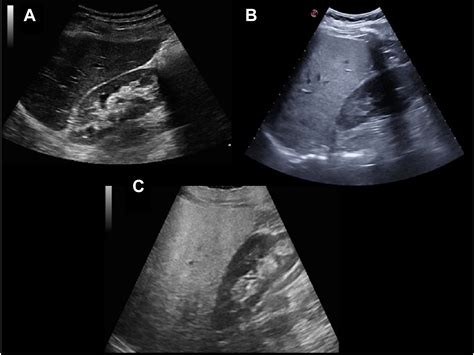

In the world of medical imaging, the liver is typically used as the "benchmark" for brightness. Healthy liver tissue has a specific texture and gray-scale appearance known as isoechogenicity. When an ultrasound technician scans the liver, they compare its brightness to the nearby kidney cortex and the spleen. If the liver appears brighter, darker, or more grainy than normal, it signals a change in the internal composition of the organ. The echogenicity of the liver is a direct reflection of how much sound energy is bouncing back to the transducer, which changes based on the presence of fat, fibrous tissue, or cellular swelling.

Radiologists categorize the liver's appearance into three primary grades based on how the echoes are reflected. Recognizing these variations is the first step in identifying underlying liver disease:

• Hyperechoic Liver: This occurs when the liver appears brighter than the kidney. It is the most common indicator of hepatic steatosis, or fatty liver disease, where fat cells infiltrate the liver tissue.

• Hypoechoic Liver: This happens when the liver appears darker than normal. This can occur in cases of acute hepatitis, where inflammation causes cellular swelling, or occasionally in specific types of infiltrative diseases.

• Hepatitis: Viral or autoimmune inflammation can change the cellular texture, sometimes resulting in a darker, "starry sky" appearance.

Healthy Liver Isoechoic Smooth, uniform gray

Mild Fatty Liver Increased (Mildly Hyperechoic) Slightly brighter than kidney

Severe Fatty Liver Markedly Hyperechoic Bright, poor visualization of vessels

Cirrhosis Coarse/Hyperechoic Nodular surface and internal brightness

Acute Hepatitis Hypoechoic Darker, "starry sky" effect